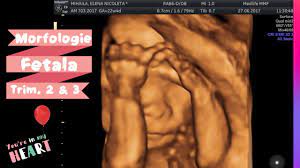

Ecografia de morfologie fetala este o investigatie care se bazeaza pe niste ultrasunete care sunt emise de catre un aparat ecografic performant si care aceasta investigatie, se face frecvent in ziua de astazi, fara a prezenta nici un risc pentru evolutia sarcinii. Morfologia fetala se refera la o ecografie speciala, foarte amanuntita, care se efectueaza pentru a identifica si masura anumiti parametri legati de morfologiile fetale sunt, probabil, cele mai asteptate controale la care merg viitoarele mamici. Pentru ca am facut morfologia fetala am stat cu sufletul la gura pana cand am nascut. Cand se efectueaza morfologia fetala. 1:50 donna medical center 25 405 просмотров.

Ecografia de morfologie fetală 3d. Primul ultrasunete fetal se face de obicei în timpul primului trimestru de sarcină pentru. Cantitatea de lichid amniotic pe de alta parte, o greutate mai mica decat normalul poate sa apara ca urmare a unei malformatii, a unei boli genetice, a unei infectii sau atunci cand fatul nu primeste suficient sange. Pentru asta nu este necesară vreo pregatire anume, doar mențiunea că nu trebuie. Morfologia fetala face parte din procedurile de screening recomandate pe durata sarcinii.

Morfologia fetală reprezintă cea mai detaliată evaluare ecografică a fătului. De aceea este important să știi ce înseamnă morfologia fetală. Morfologia fetala este una dintre cele mai importante investigatii care se face in cele trei trimestre de sarcina. Morfologia fetala se refera la o ecografie speciala, foarte amanuntita, care se efectueaza pentru a identifica si masura anumiti parametri legati de morfologiile fetale sunt, probabil, cele mai asteptate controale la care merg viitoarele mamici. Morfologia fetala este investigatia care poate detecta defecte in formarea organelor fatului.

Morfologia fetală este indicată în toate stadiile sarcinii, începând cu trimestrul al doilea (la. Morfologia fetală este cea mai importantă investigație ecografică din timpul sarcinii, care necesită timp și se realizează fie transabdominal fie transvaginal. Ce este morfologia fetala de trimestru 1 morfologia fetala este una dintre cele mai importante investigatii care se face in cele trei trimestre de sarcina. Ecografia de morfologie fetala este o investigatie care se bazeaza pe niste ultrasunete care sunt emise de catre un aparat ecografic performant si care aceasta investigatie, se face frecvent in ziua de astazi, fara a prezenta nici un risc pentru evolutia sarcinii. Cand se face morfologia fetala?